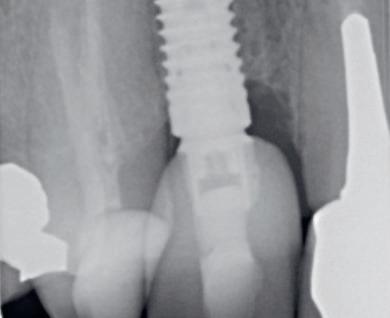

Een 48-jarige gezonde vrouw presenteerde zich in de nazorgfase 2 jaar na initiële behandeling met pockets van 6–7 mm en furcatieproblematiek bij de 47 en 46 (afbeelding 1.1 en 1.3). Bloeding bij sonderen was aanwezig, maar de patiente wilde geen chirurgische behandeling. Ze hield er een keurige mondhygiëne op na en kwam trouw iedere drie maanden voor nazorg.

De pockets werden onder lokale anaesthesie behandeld met een combinatie van ultrasoon en handinstrumentarium volgens de hierboven beschreven methode. De natriumhypochloriet/aminozuur-gel werd vijfmaal aangebracht en na iedere applicatie mechanisch verwijderd. Daarna werd de pocket gevuld met cross-linked hyaluronzuur.

Na 6 maanden was de pocketdiepte teruggebracht tot 3 mm en was er geen bloeding na sonderen waarneembaar. Een recessie van 2 mm was aanwezig. Röntgenologisch was er nieuw bot zichtbaar (afbeelding 1.2 en 1.4).